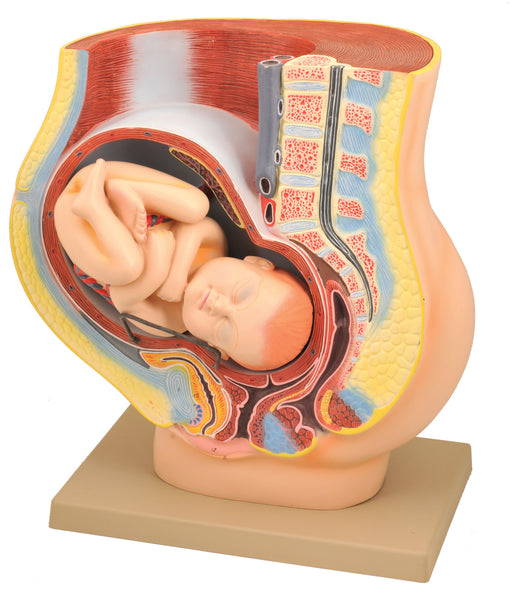

Model, Human Female Pelvis, Pregnancy with Fetus

Life Size Removable baby 15" h x 12x l x 9" w Life size representation of a median section through the female pelvis in the 9th month of pregnanc...

View full detailsAM120AS -